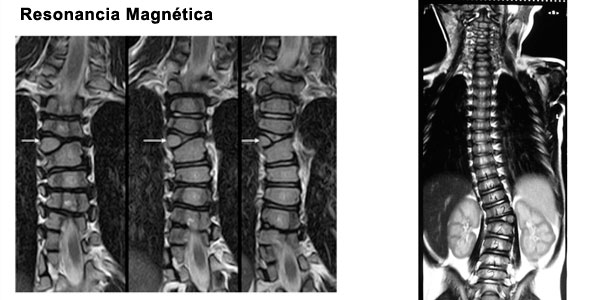

Al tener un diagnostico de escoliosis congenita debe descartarse otras malformaciones en otros organos y/o sistemas:

Anomalias intraespinales.

Es necesario evaluar con detalle al niño y solicitar estudios de imágenes que nos puede mostrar la estructura de la columna en forma completa.

Paciente de 1 año y 8 meses con escoliosis congénita progresiva, se realizó resección de hemivertebra con colocación de tornillos transpediculares